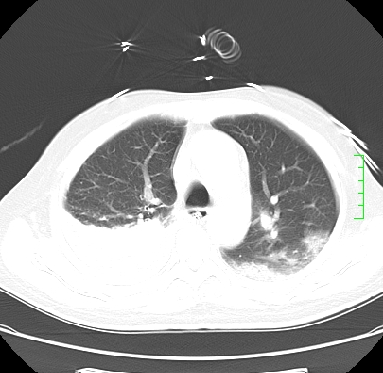

icu病人,几天都没明确诊断。m,76y,咳嗽、咳痰1周,伴气促,右胸痛入院,pe:t38.3c p135 r25 bp135/85。双肺可闻及大量湿罗音,心、腹未见明显异常。诊断:1心衰?2肺部感染?3冠心病?

11号ct

双肺感染性病变,下叶膨胀不全,胸水,左室大。

1)两肺感染性病变(右肺下叶肺脓肿可能)。2)双侧胸腔积液,以右侧为甚。

ards,肺感染性病变,右下叶实变,双侧胸腔积液,右侧为著,叶间胸膜积液,右上肺陈旧性tb纤维灶,左室大。